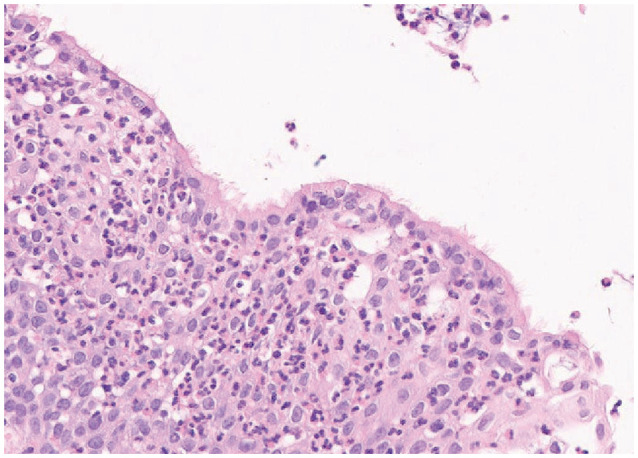

Recurrence of Rathke's cleft cysts (RCC) following surgery is not uncommon. We present a 33-year-old male patient with chronic headache and visual disturbances whose MRI showed mostly cystic, suprasellar mass with peripheral enhancement. Endoscopic extended transsphenoidal approach and tumor resection was performed and RCC was pathologically confirmed postoperatively. Early recurrence was first suspected at 3 months following surgery, and his serial MRIs showed a recurred mass without associated clinical symptoms. Upon further histopathological study, extensive squamous metaplasia and high Ki-67 were seen. Also, in this study, we discuss important factors associated with cyst recurrence following surgery.